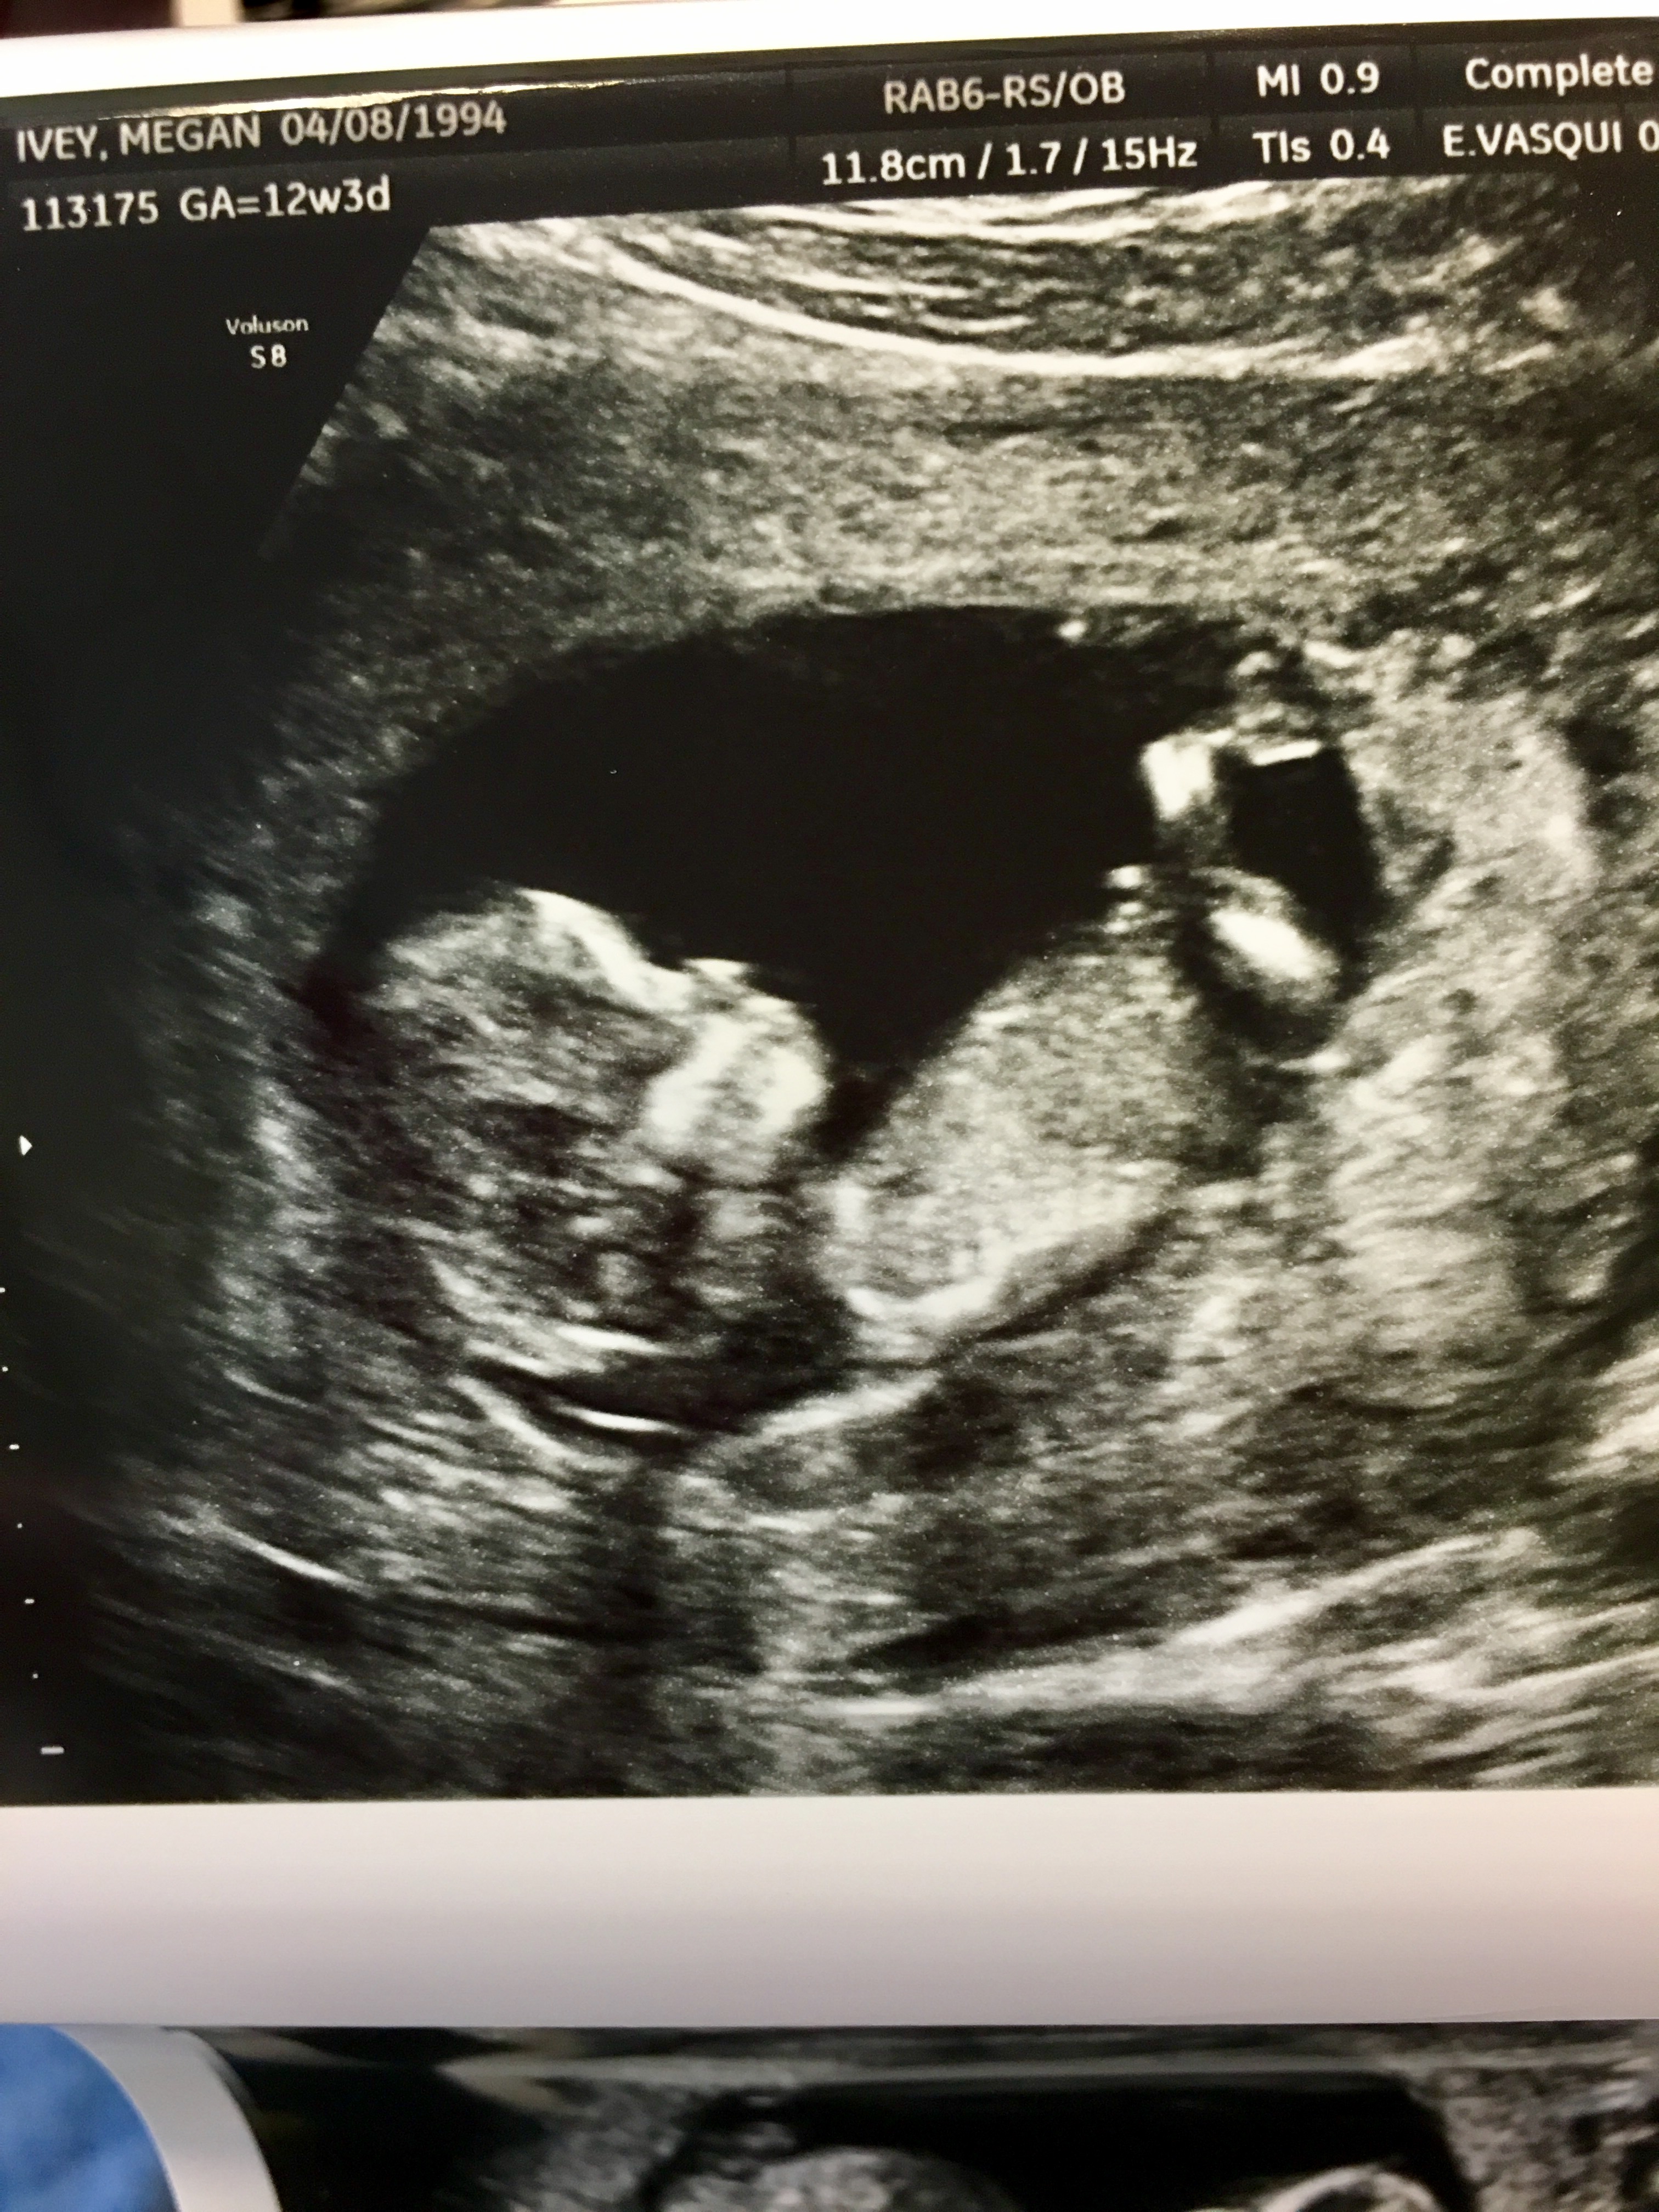

12w3d NT Scan- possible boy?

Went for my Nt scan today & nurse took a guess for a boy! I wish I had gotten the better views that she did show me, but I was too caught in the moment. The last picture (horrible quality, I know) was a screenshot of the video on my phone.

I know there's many theories such as the nub theory, skull theory, & ramzi's theory- being a first time mom, I have no clue what I'm looking for! Thoughts on gender? 🤗

Attachment 37042Attachment 37043Attachment 37044